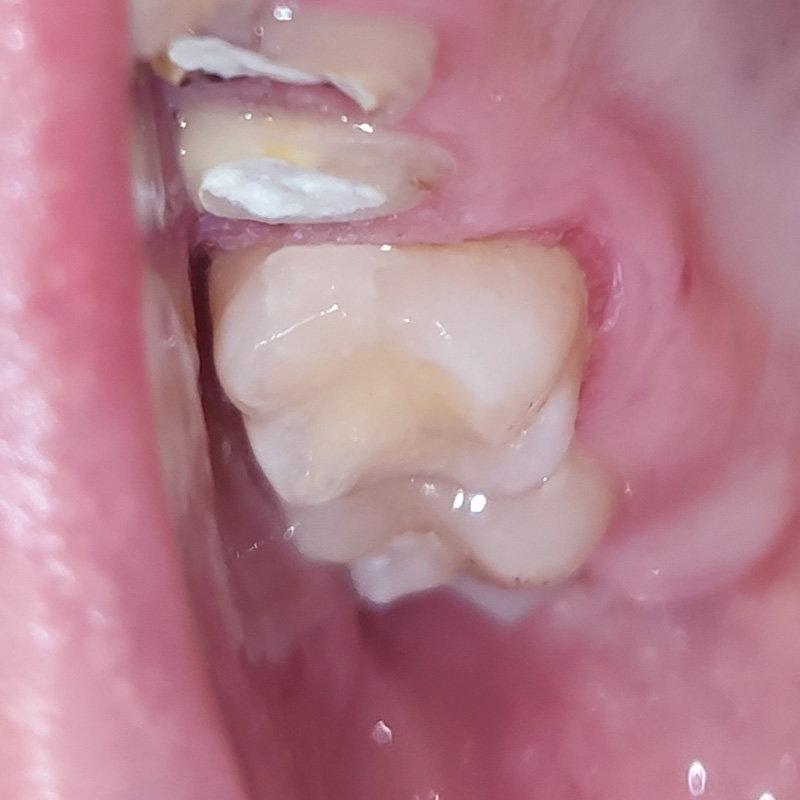

Пациентка обратилась в «Стоматологию Комфорта» с жалобой на отсутствие зубов верхней челюсти. По результатам обследования врач стоматолог-ортопед, хирург-имплантолог Мельников Алексей Владимирович назначил имплантацию по методу «all-on-4». По истечении 6 месяцев после операции проведено обслуживание условно-съёмного протеза. Также врач начал восстановление нижней челюсти коронками в комбинации с бюгельный протезом.

- восстановление нижней челюсти коронками в комбинации с бюгельным протезом.